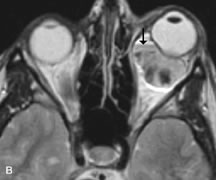

On MRI, uveal melanomas have a typical appearance that helps to differentiate them from other primary and secondary intraocular tumors as well as choroidal detachments. Pigmented melanomas are hyperintense on Tl-weighted images, hypointense on T2-weighted studies, and hyperintense on proton density–weighted examinations (Fig. 24).30,31,50,80–82 These signal characteristics have been attributed to the paramagnetic properties of melanin because of stable free radicals that shorten the T1 and T2 relaxation times. Moderate enhancement is seen on postgadolinium T2-weighted images. Gadolinium-enhanced T1-weighted images are particularly sensitive in detecting choroidal melanomas.83 MRI may be less sensitive in detecting extrascleral extension of tumor than echography performed by an experienced ultrasonographer.84

Fig. 24. A. T1- and (B) T2-weighted MR scans demonstrate a small nodular intraocular mass (arrows) that is very hyperintense on the T1-weighted scan and hypointense on the T2-weighted image. This signal intensity pattern is due to the presence of free radicals within melanin granules. C and D. Postcontrast fat-suppressed T1-weighted scans demonstrate homogeneous intense enhancement of the lesion and no evidence of seleral penetration or optic nerve invasion.